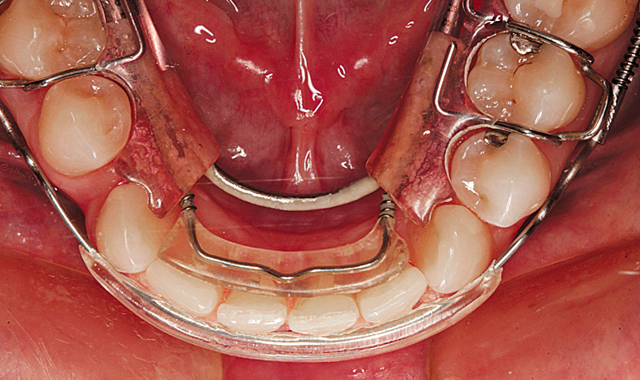

The mandibular aligner is shown in place after 12 weeks in Figure 10. Figure 11 demonstrates the maxillary incisal view showing the aligner removed.

Fig. 10

Fig. 11

Note that the left canine is still slightly rotated and a small diastema exists between the right lateral and central incisors. In Figure 12, you can see that the mandibular incisors are well aligned with only a slight diastema remaining between the right lateral and central incisors. In the retracted facial view in Figure 13, you can see that a much improved alignment has been achieved.